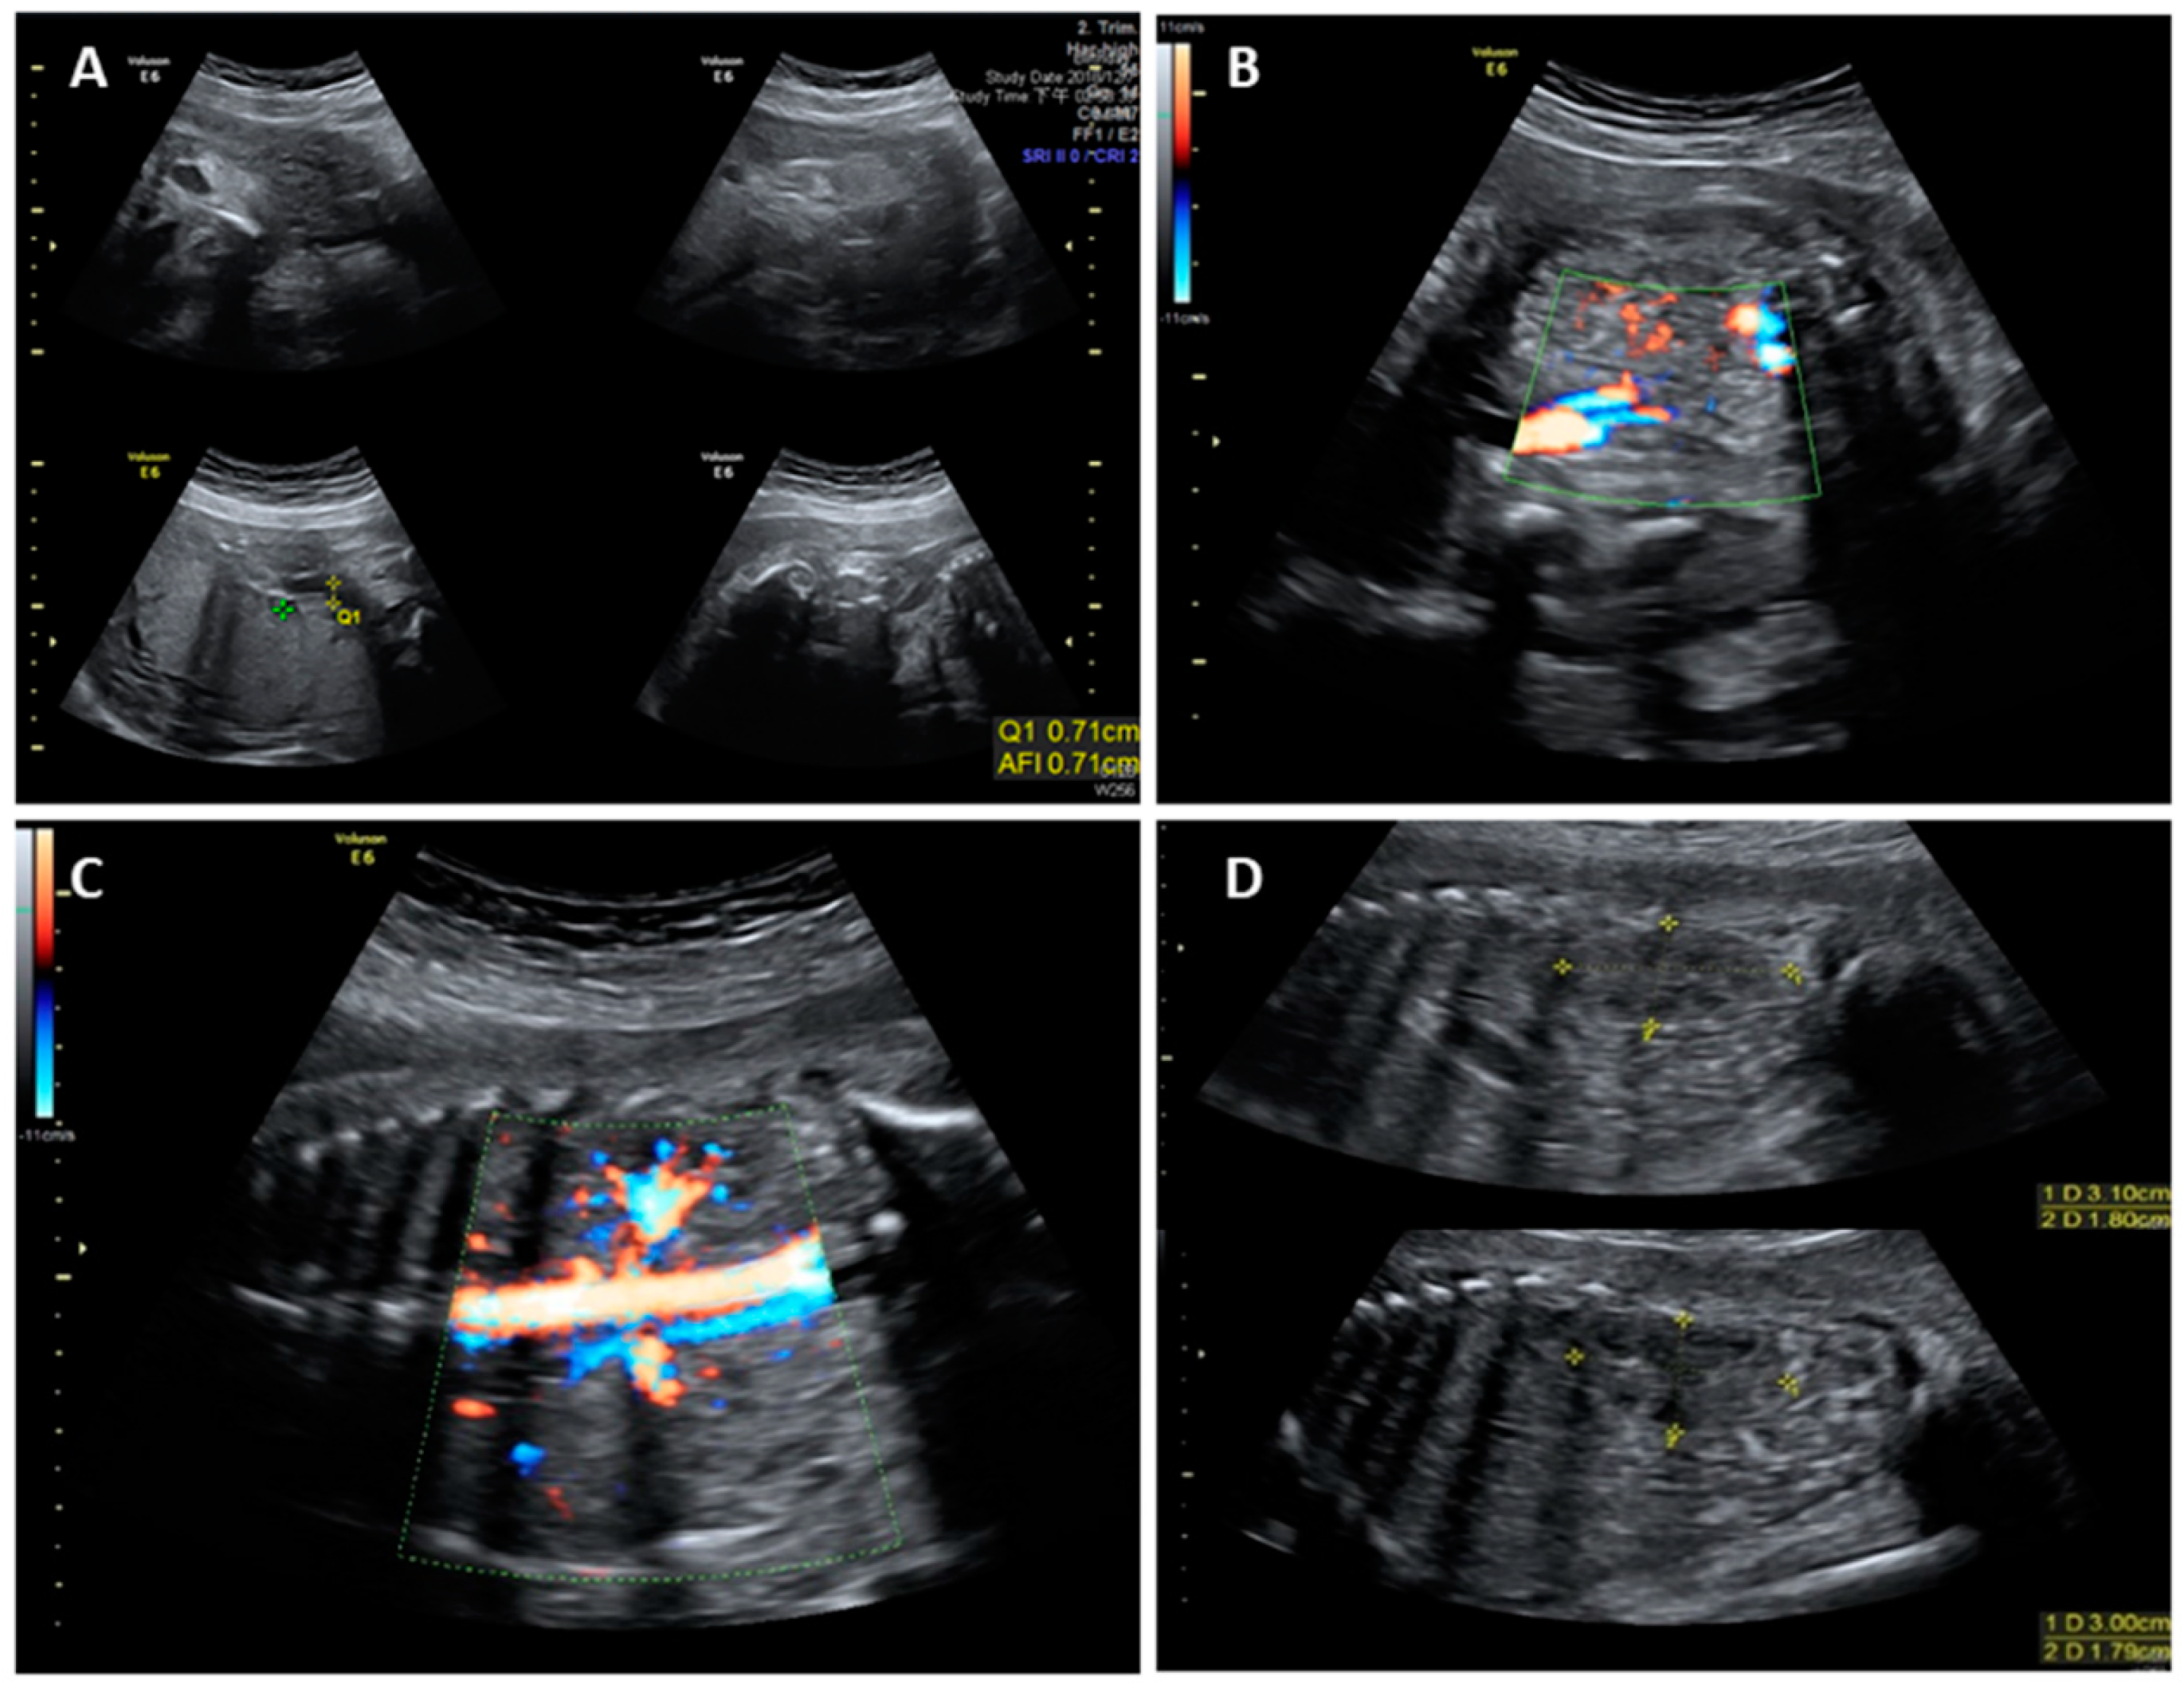

2. Case Report